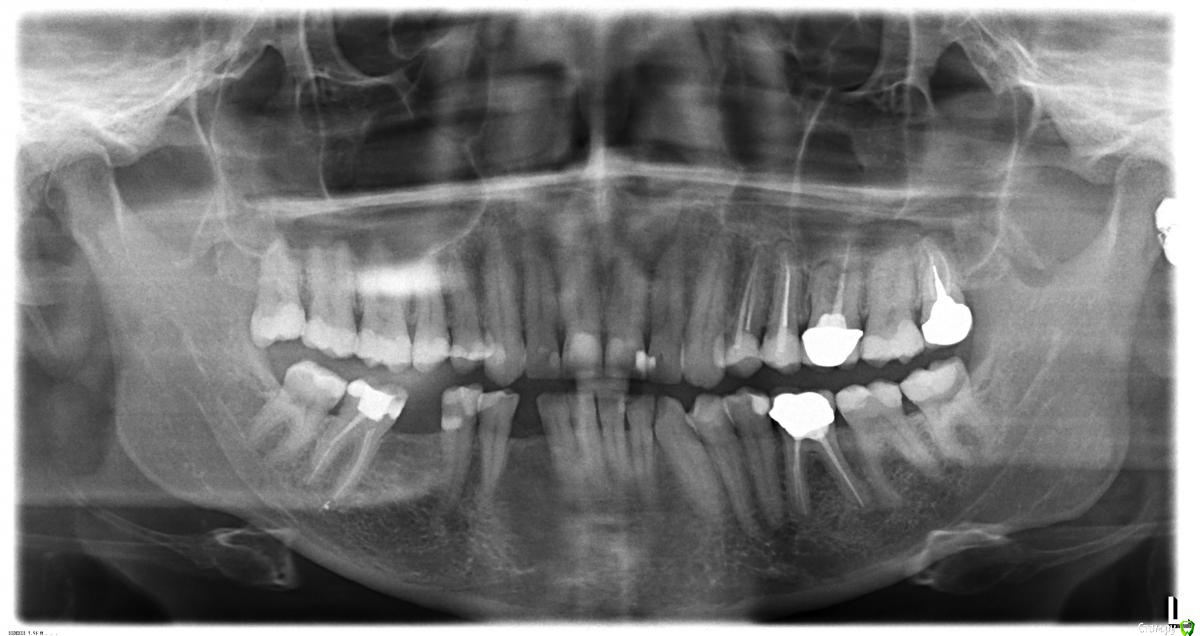

vitavita Опубликовано 5 февраля, 2015 Автор Поделиться Опубликовано 5 февраля, 2015 Вот загружаю еще панорамный снимок от 16 апреля 2014 года. Но там никакой кисты и не видно. Хотя очевидно что она там была - такие кисты за полгода не вырастают. Ссылка на комментарий

vitavita Опубликовано 5 февраля, 2015 Автор Поделиться Опубликовано 5 февраля, 2015 http://s018.radikal.ru/i502/1502/f9/d092b41cc891.jpg Ссылка на комментарий